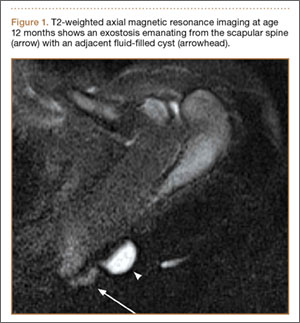

The patient returned to clinic at age 31 months with a new complaint of scant drainage of serous fluid from a pinprick-sized hole located just superolateral to the scapular mass. The child’s mother reported daily manual expression of fluid from the mass via the hole, without which the mass would enlarge. There were no local or systemic signs of infection. A repeat MRI again revealed an exostosis with an adjacent cystic mass with interval enlargement of the cyst (Figure 2). At age 4.5 years, the decision was made to proceed with excision of the osteochondroma and adjacent cystic mass.